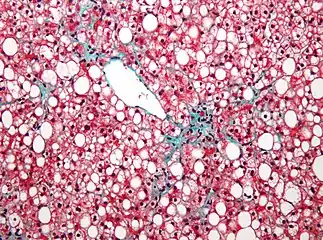

| Micrograph demonstrating marked (macrovesicular) steatosis in non-alcoholic fatty liver disease. Masson's trichrome stain. | |

Steatosis reflects an impairment of the normal processes of synthesis and elimination of triglyceride fat. Excess lipid accumulates in vesicles that displace the cytoplasm. When the vesicles are large enough to distort the nucleus, the condition is known as macrovesicular steatosis; otherwise, the condition is known as microvesicular steatosis. While not particularly detrimental to the cell in mild cases, large accumulations can disrupt cell constituents, and in severe cases the cell may even burst.

Macrovesicular steatosis

Macrovesicular steatosis is the more common form of fatty degeneration and may be caused by oversupply of lipids due to obesity, obstructive sleep apnea (OSA),[8] insulin resistance, or alcoholism. Nutrient malnutrition may also cause the mobilisation of fat from adipocytes and create a local oversupply in the liver where lipid metabolism occurs. Excess alcohol over a long period of time can induce steatosis. The breakdown of large amounts of ethanol in alcoholic drinks produces large amounts of chemical energy in the form of NADH, signalling to the cell to inhibit the breakdown of fatty acids (which also produces energy) and simultaneously increase the synthesis of fatty acids. This "false sense of energy" results in more lipid being created than is needed.